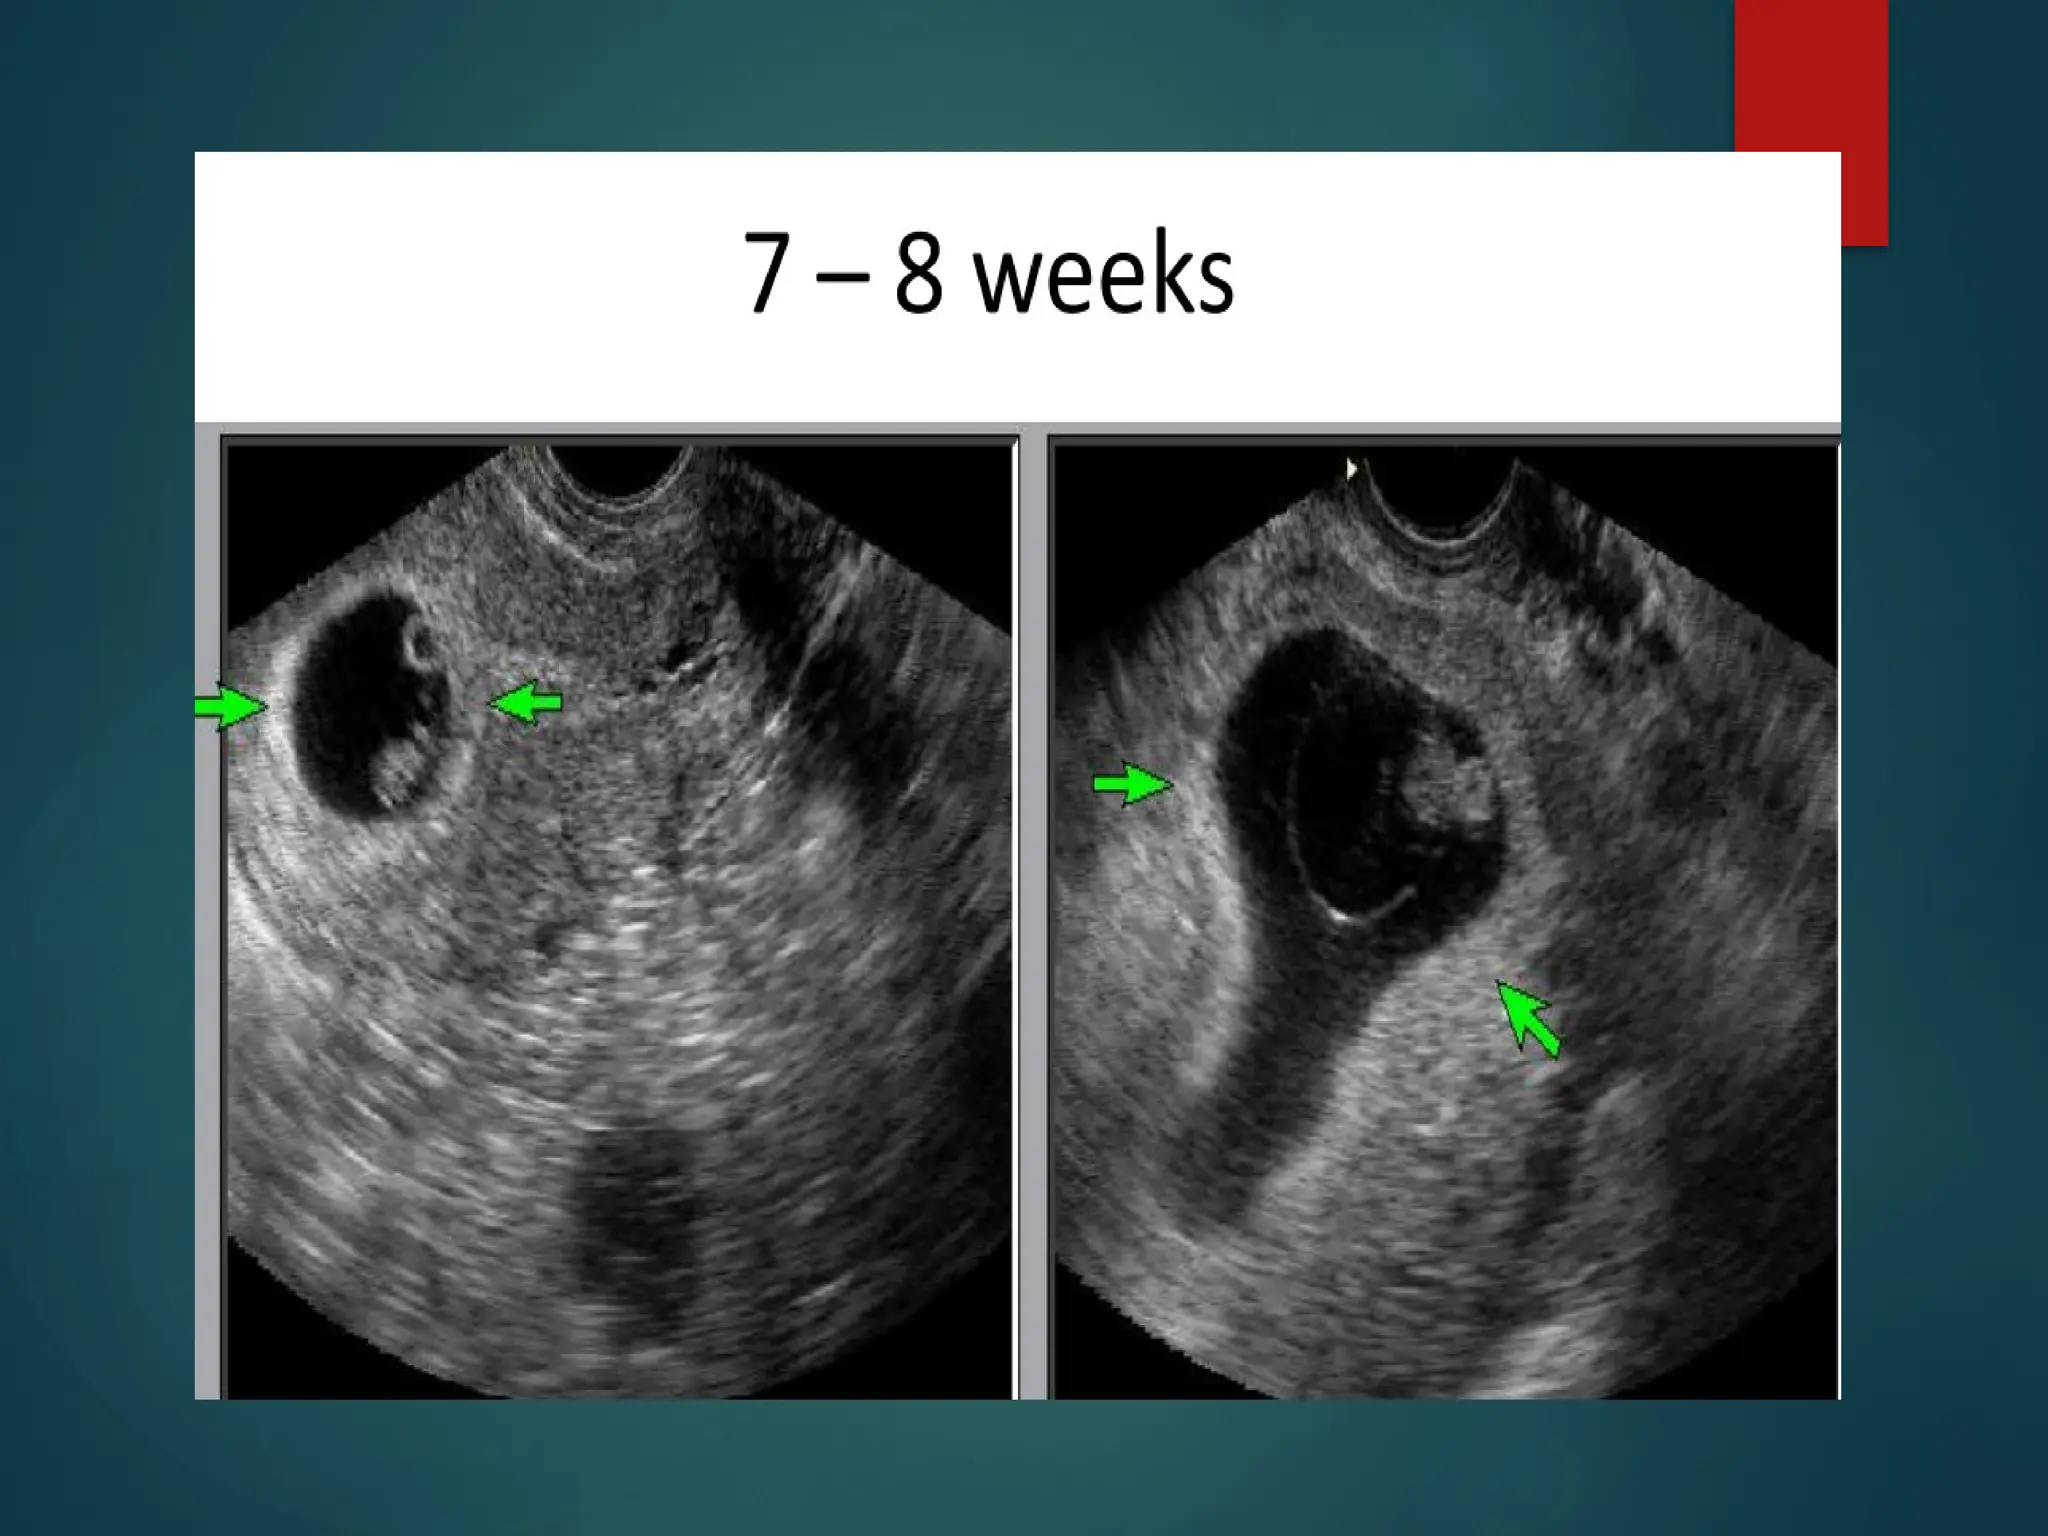

• 7-8 weeks

• CRL is between 11-16 mm

• cephalad and caudal poles can be identified